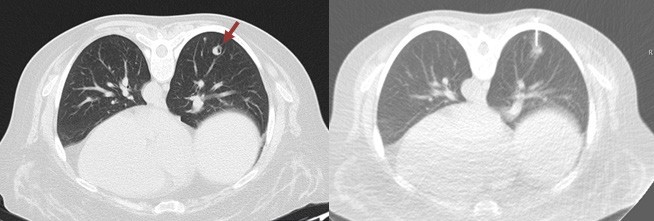

We present a case of a 47-year-old non-smoker, non- drinking Caucasian woman recently diagnosed with invasive squamous cell carcinoma of the tongue (cT2N0Mx). A decision was made to perform right hemiglossectomy with tumor exeresis and radical cervical lymphadenectomy. CT scan of the head, neck and chest were also performed for cancer staging. High resolution CT scan revealed three round subpleural nodules of uncertain etiology, located posterior and inferiorly in the right upper lobe and superiorly in the right lower lobe, measuring 6.8, 8.6 and 9 mm, the latter presenting cavitation. (Figure 1). No hilar or mediastinic lymphadenopathies were observed, and there were no pleural or pericardial effusions. No other remarkable changes were seen in the mediastinum or the lungs. The patient remained asymptomatic. CT guided transthoracic biopsy was required for nodule characterization, and biopsy of the 9 mm cavitary lung nodule (Figure 2) revealed pulmonary parenchyma with mostly preserved alveolar structure, partially occupied by spindle cell proliferation, without pleomorphism, necrotic areas, atypia or mitotic figures.

Figure 1: Axial chest CT scan showing three round subpleural nodules of uncertain etiology, located posterior and inferiorly in the right upper lobe and superiorly in the right lower lobe, measuring 6.8, 8.6 and 9 mm, the latter presenting cavitation.

Imaging features of BML are non-specific.2 Lung involvement in BML may appear as lung nodules on chest radiography or CT, ranging from solitary sub-centimetric lesions to multiple lesions similar to malignant metastases.2,8 The usual presentation is the presence of bilateral, well-circumscribed, non-calcified nodules diagnosed incidentally.2,3 Cavitation of these lesions may occur,2,3 as in our clinical case. More rarely, pneumothorax may take place, along with occasional cases of miliary pattern and pattern simulating interstitial disease.2 CT and MR imaging studies are often used to detect and describe these pulmonary nodules, which usually present homogeneous enhancement and non-specific appearance.2 As such, a list of differential diagnosis must be taken into account when considering possible BML lung nodules, including lung malignant metastases and, more rarely, infectious pulmonary granulomas, rheumatoid nodules, sarcoidosis and amyloidosis.2 In this clinical case, given the previous oncologic diagnosis and no known history of uterine leiomyomas, our main concern was to rule out malignant nature of these lung nodules, due to the possibility of distant metastases of oral squamous cell carcinoma.9,10 Imaging-guided biopsy is most often required to get a definitive diagnosis.